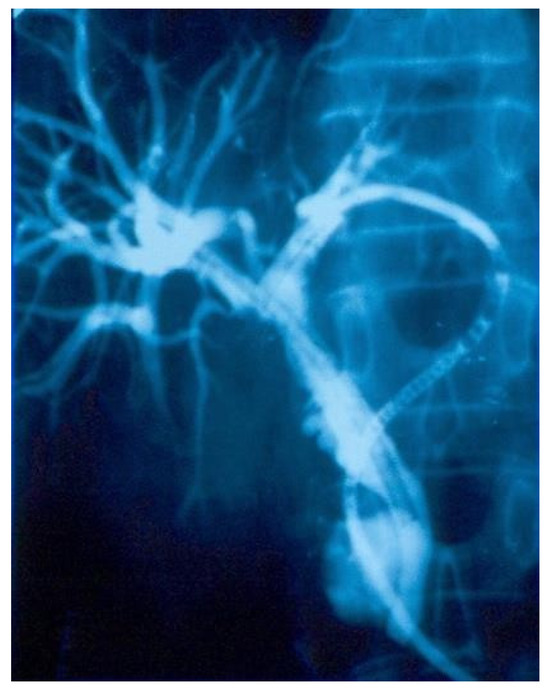

From this lot we present an interesting case of biliary fistulae of the left hepatic duct that was submitted in our service from another clinic, for surgical reevaluation. The CBD lesion was resolved there with the aid of a choledochoduodenostomy which, unfortunatelly, in the postoperative stage developed an anastomosis stenosis and a consecutive obstructive jaundice. Our solution to resolve this complication was, after the dilatation and recalibration of the choledochoduodenal anastomosis, to perform a double axial transanastomotical drainage of the left and right hepatic duct, this drainage being exteriorized in a transparietohepatic and transomphalic way, virtually without any suture of the fistulae. The reasons behind this decision were: the fragility of the left hepatic duct due to external fistula, the inability to a good cicatrisation, the clear advantage of an axial external biliary drainage of being able to recalibrate, decompress and protect the suture. Therefore, we achieved perfect cicatrisation of the fistulae after 3 months of continuous axial transcholedocohepatic prothesis (Figure 1). In this group of cases, the biliodigestive anastomoses were later on complicated by early recurrent fistulae in 2 cases and with stenosis in 1 case.

Figure 1.

C-Arm colangiographic control in preparation for patient discharge, performed after 3 months of continuous drainage. The slide exhibits no signs of fistulae and therefore a good choledochoduodenal anastomosis was achieved.